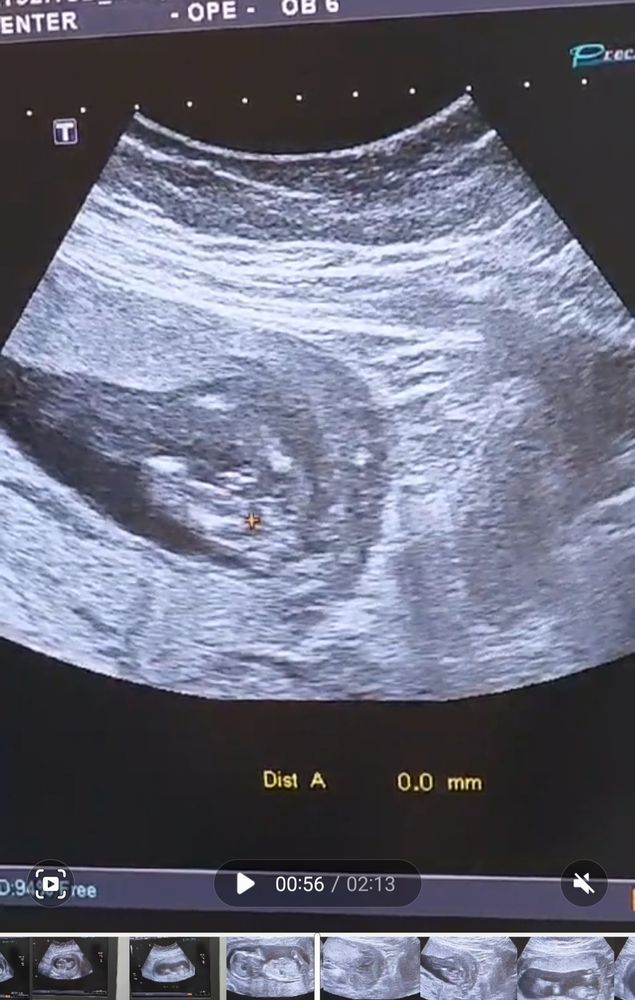

Так выглядит мой мальчик😁

Сын! У нас будет сын !! Пол малыша на 1 скрининге